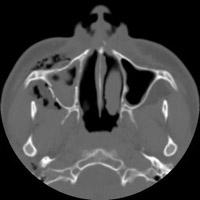

- Click on the image for a larger versionCAxial CT. This image through the maxillary sinuses reveals a fracture of the lateral wall of the right maxillary sinus, the source of the emphysema